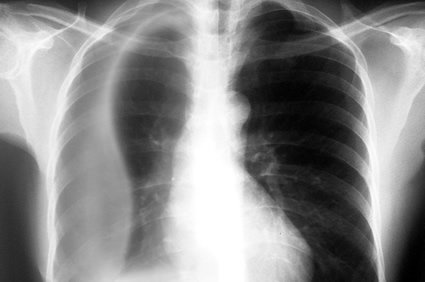

Como o médico diagnostica o derrame pleural?

O médico deverá fazer um levantamento do histórico clínico do paciente e dos sintomas que ele relata, bem como fazer um exame físico que deverá incluir auscultar seu tórax com um estetoscópio. Para confirmar o diagnóstico, precisará fazer exames de imagem, como radiografias do tórax em várias posições, tomografia computadorizada e ultrassonografia.